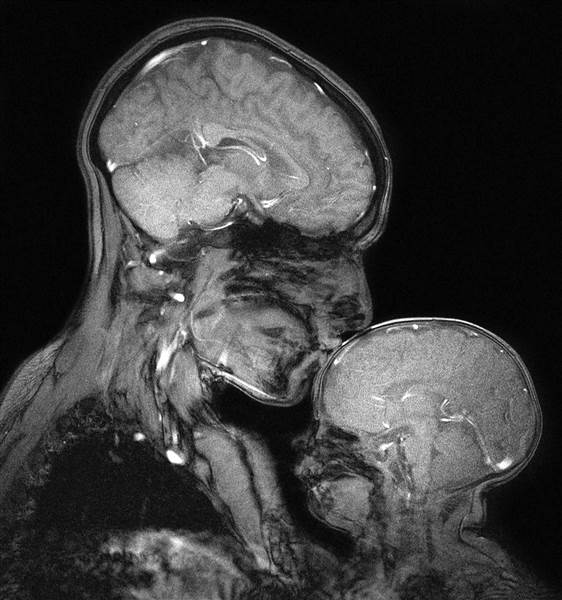

Bức ảnh chụp cộng hưởng từ được cho là đầu tiên thể hiện tình cảm mẹ con. Điều hấp dẫn trong bức ảnh chỉnh là mối quan hệ nó diễn tả. Hình ảnh người mẹ đang ôm ấp và hôn cậu con trai bé nhỏ mang nhiều ý nghĩa.

Hình ảnh chụp cộng hưởng từ (MRI) cung cấp cái nhìn thoáng qua về bên trong cơ thể của chúng ta, nhưng cũng có thể chụp lại được một tình yêu thuần khiết. Chuyên gia thần kinh học Rebecca Saxe đã chứng minh điều này khi chia sẻ bức ảnh đang ôm ấp và hôn cậu con trai 2 tháng tuổi Percy của mình vài năm trước.

"Điều hấp dẫn trong bức ảnh là mối quan hệ mà nó diễn tả", Saxe nói với TODAY. Hình ảnh này không được thực hiện để chẩn đoán bất kỳ vấn đề nào, nhưng chỉ vì Saxe và các đồng nghiệp của cô muốn nhìn thấy nó.

Saxe sử dụng máy chụp cộng hưởng từ không bức xạ để không gây hại cho mẹ và bé.

Nhiều người tập trung vào so sánh hình ảnh bộ não của người lớn và trẻ em: "Một số người nhìn vào bức ảnh và thấy phần lớn sự khác biệt: Xương sọ của cậu bé mỏng làm sao, không gian nhỏ thế nào giữa thế giới bên ngoài và não cậu bé. Nó chỉ là một vỏ sò rất mỏng và mong manh", Saxe nói.

"Mặt khác, bạn có thể nhìn vào nó và xem điều tương tự như thế nào đối với bộ não của người mẹ. Kích thước gần bằng bàn tay của cậu bé".

Một khác biệt lớn là não của bé hầu như không có myelin - "lớp cách điện" làm nhiệm vụ truyền thông điệp bên trong não của bạn, theo Saxe.

Saxe, giáo sư về thần kinh học ở MIT, nghiên cứu cách não chúng ta xây dựng tư tưởng và ngôn ngữ. Cô ấy đặc biệt quan tâm đến cách chúng phát triển trong suốt thời thơ ấy. Điều đó có nghĩa là lén nhìn vào đầu của đứa trẻ với sự trợ giúp từ hình ảnh cộng hưởng từ, chi tiết bên trong bộ não được thể hiện rõ. Saxe sử dụng máy MRI của phòng thí nghiệm "cả ngày, mỗi ngày".

Sau khi sinh con đầu lòng, Saxe đã dành nhiều giờ nằm trong máy chụp cộng hưởng từ cùng cậu bé để theo dõi não của con phát triển. "Giống như bất cứ người mẹ nào, tôi yêu trẻ con một cách điên rồ. Nhưng tôi cũng phải quan sát bộ não của con phát triển ngay trước mắt mình", Saxe cho biết.

"Nó giống như trải nghiệm của tôi về việc làm mẹ và trải nghiệm của tôi về việc trở thành một nhà thần kinh học" - đó là cách cô ấy bắt đầu nghĩ đến việc chụp MRI hai mẹ con. Cô đã phải mất vài tháng làm việc với kỹ thuật viên để tìm ra cách chụp ảnh mẹ con bằng máy cộng hưởng từ.

Hơn hai ngày, cô và Percy đã dành vài giờ để chụp được những bức ảnh như ý (MRI không sử dụng bức xạ và không có khả năng gây hại).

"Nó rất, rất khó để thực hiện. Bạn phải giữ nguyên trong vài phút để có được hình ảnh. Cố gắng thuyết phục một đứa trẻ", Saxe nói.

Máy hoạt động ồn ào, vì vậy Saxe phải đeo tay nghe trong khi Percy dùng miếng đệm tai. Cả hai phối hợp tốt và cậu bé đang ngủ trong bức ảnh mà bạn nhìn thấy.

Phải mất 25 lần thử mỗi ngày để tạo ra bức ảnh đó - được lựa chọn là tốt nhất trong các bức ảnh chụp được. "Tôi nghĩ nó đẹp. Tôi không thể rời mắt khỏi nó", Saxe chia sẻ.